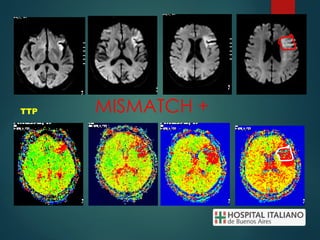

MISMATCH +

DWI

TTP

MAPAS DE PERFUSION (PWI)

MISMATCH (-)

PERFUSIÓN CEREBRAL - CBV(volúmen sanguíneo cerebral). - CBF (flujo sanguíneo cerebral) - TTP (tiempo al pico). - TTM ó MTT ( Tiempo promedio de tránsito vascular o tiempo de tránsito medio).